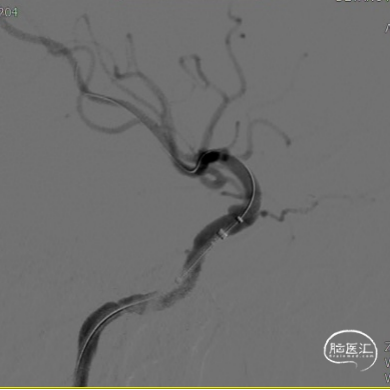

(A)

(B)

(C)

(D)

(E)

(F)

A:准备定位后打开Surpass Streamline头端于Catalyst 5。

B:缓慢回撤Catalyst 5,逐渐释放Surpass Streamline。

C:支架收尾。

D:Catalyst 5中间导管进行支架内按摩。

E:动脉瘤腔内可见造影剂滞留。

F:动脉瘤腔内可见造影剂滞留(另一角度)。